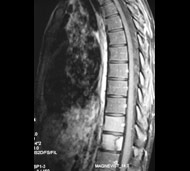

Спинальна магнітно-резонансна томографія (МРТ). Замість радіаційного випромінювання в МРТ використовуються потужні магнітні і радіохвилі для отримання зображення поперечного перерізу хребта. МРТ чітко відображає спинний мозок і нерви і забезпечує краще зображення пухлин кісток, ніж комп'ютерна томографія (КТ). Вам можуть ввести в вену кисті або передпліччя контрастну речовину, яка висвітлює деякі пухлини. Крім цього, використовують сканери з високою інтенсивністю сигналу для виявлення невеликих пухлин, які можна не помітити.